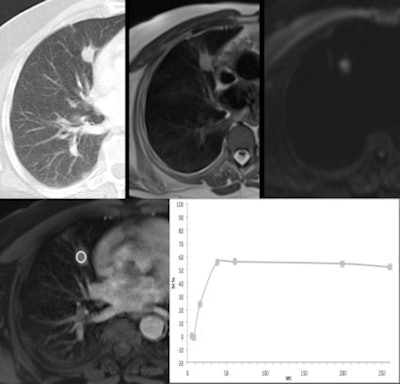

"In this study, we propose a technique for contrast-enhanced MRI of the chest that can be applied in the clinical scenario," he explained. "It allows us to visually evaluate enhancement pattern/progression and to obtain quantitative perfusion analysis of lung lesions within the same method. A volumetric-interpolated T1-weighted GE sequence, already available in most commercial MRI systems, is applied within a strategy adapted to the pulmonary circulation."

The aim was to propose a technique for evaluation of pulmonary lesions using contrast-enhanced MRI and to assess morphological patterns of enhancement and correlate quantitative analysis with histopathology. Volumetric-interpolated T1-weighted images were obtained during consecutive breath-holds after bolus triggered contrast injection.

Volume coverage of first three acquisitions was limited (higher temporal resolution) and the last acquisition was obtained at the 4th minute. Two radiologists individually evaluated the patterns of enhancement. Region-of-interest-based signal intensity (SI)-time curves were created to assess quantitative parameters.

A fast volumetric sequence with high spatial and contrast resolution was used to perform contrast-enhanced MRI of focal lung lesions within a strategy adapted to the pulmonary circulation, according to the authors. Quantitative analysis was highly sensitive to detect malignancy, in agreement to what has been described for other imaging methods as dynamic CT and PET.